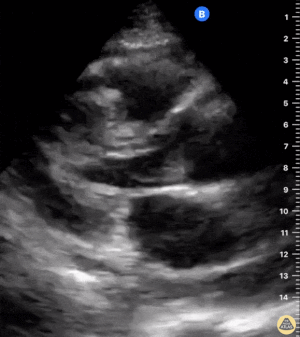

Sağ ventrikül fonksiyonunun değerlendirilmesi

Sağ ventrikül, önceki bölümde anlatılan temel kardiyak pencereler kullanılarak değerlendirilebilir. Normalde sağ ventrikül düşük basınçlı bir odacıktır ve sol ventriküle kıyasla daha küçük görünür.

Sağ ventrikül disfonksiyonunda özellikle şu bulgulara bakılır:

Sağ ventrikül dilatasyonu

Septal bombeleşme (septal bowing)

Kısa aks görüntüsünde, pulmoner arter basıncının artmasına bağlı olarak sağ ventrikül genişledikçe interventriküler septum sol kalbe doğru bombeleşir. Bu durum sol ventrikülde D-şekilli görünüm (D-sign) oluşturur.

Apikal dört boşluk görüntüsünde sağ ventrikül normalde sol ventrikülün yaklaşık üçte ikisi büyüklüğünde olmalıdır. Eğer iki ventrikül aynı boyutta görünüyorsa bu durum anormal kabul edilir ve dilatasyon düşündürür.

Bir diğer önemli bulgu McConnell belirtisidir. Bu bulgu, sağ ventrikül serbest duvarında hipokinezi bulunurken apeksin korunmuş olması şeklinde tanımlanır.